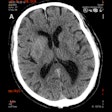

IR with CAD permits ultralow lung CT dose